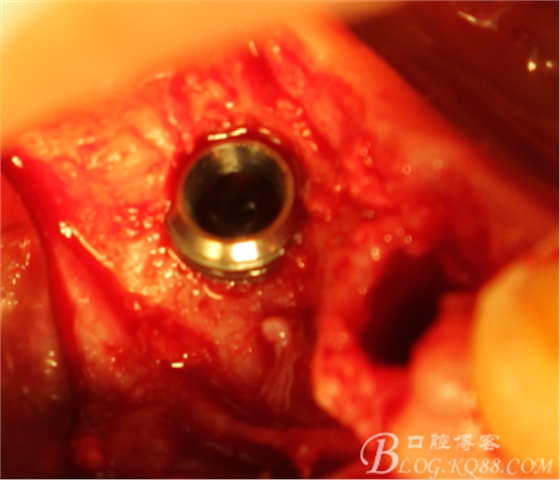

植入植體

切開(kāi),成骨情況良好,

搔刮C5頸部肉芽

上愈合基臺(tái),間斷縫合關(guān)閉創(chuàng)口,頰側(cè)牙齦部分恢復(fù)形態(tài)